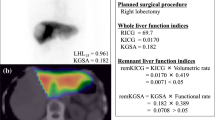

All patients underwent HBS to evaluate total and FRL function prior to resection as described previously [9, 10]. Briefly, dynamic acquisitions were obtained using a dual head SPECT-CT camera (Siemens Symbia T16) for 38 frames of 10 s/frame after injection of 200 MBq 99m Tc-mebrofenin (Bridatec, GE Healthcare) in order to calculate the hepatic uptake rate (Fig. 1a). Subsequently, SPECT was performed (60 projections of 8 s/projection, 128 matrix) which was used for the three-dimensional assessment of liver function and calculation of functional liver volume. This was combined with low-dose, non-contrast-enhanced CT for attenuation correction and anatomical mapping. Finally, dynamic acquisitions were obtained (15 frames; 60 s/frame, 128 matrix) to evaluate biliary excretion.

Data were processed on a Hermes workstation (Hermes Medical Solutions). Geometric mean datasets of the anterior and posterior acquisitions were used for the analysis [10]. Regions of interest (ROI) were drawn delineating the liver, the left ventricle and aorta (representing the blood pool), and the total field of view (FOV), from which time-activity curves were created (Fig. 1b).

Total liver function (TLF) was represented by the mebrofenin uptake rate (MUR; %/min). This was calculated as an increase of 99mTc-mebrofenin uptake over a time period of 200 s as described by Ekman et al [29].

The FRL was defined on the planned resection and was delineated manually on the SPECT-CT images to calculate its functional share from HBS (FS HBS), which was defined as the fraction of counts within the FRL (Fig. 1c). Subsequently, this functional share fraction was multiplied by the TLF to calculate the FRL function (fMUR; %/min).

For the calculation of the functional share from MRI (FS MRI), the FRL was manually delineated in the last dynamic (showing the largest contrast) using an ROI drawing tool. FS MRI was calculated as the summed Ki values in the FRL divided by the sum of Ki values over all voxels of the liver. Additionally, the FRL function from MRI was calculated as mean Ki in the delineated FRL region (fKi). Similarly, the mean ME and MSI were calculated over the FRL region.

The mean MUR for the total liver averaged over all patients was 15.1 (± 3.4) %/min. The mean Gd-EOB-DTPA uptake rate of the whole liver (Ki) averaged over all patients was 7.0 (± 2.4) per minute. There was a strong correlation between the MUR and Ki (Pearson r = 0.70, p = 0.001, n = 20) (Fig. 4).

Functional share and future remnant liver function

There was a strong agreement between the functional shares from HBS (FS HBS) and MRI (FS MRI) (ICC = 0.944, 95% CI 0.863–0.978, n = 20). A Bland-Altman plot is presented in Fig. 5. The mean difference in the functional share between FS HBS and FS MRI was 2.6% and the 95% limit of agreement was ± 14.3%.

Additionally, there was a strong correlation between the FRL function measured from HBS (fMUR) and MRI (fKi) (Pearson r = 0.89, p < 0.001, n = 20) (Fig. 6).